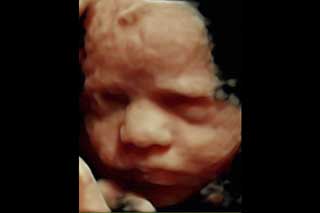

La evaluación 3D se basa en la obtención de imágenes 3D de algunas partes fetales, especialmente el rostro.

Reconstrucción digital de imágenes para formar una sola imagen en 3 dimensiones (3D), permitiendo así poder visualizar el rostro de su bebé.

La ecografía 3D es aquella que permite a usted ver la superficie corporal de su bebé, esto permite observar detalles como: labios, nariz, pómulos, frente, manos, entre otras.

Para lograr esto es necesario que se cumplan muchas condiciones como por ejemplo que el bebé no este mirando hacia atrás, que la placenta, el cordón o las extremidades no le tapen su rostro, así como que el líquido amniótico esté en cantidad suficiente.